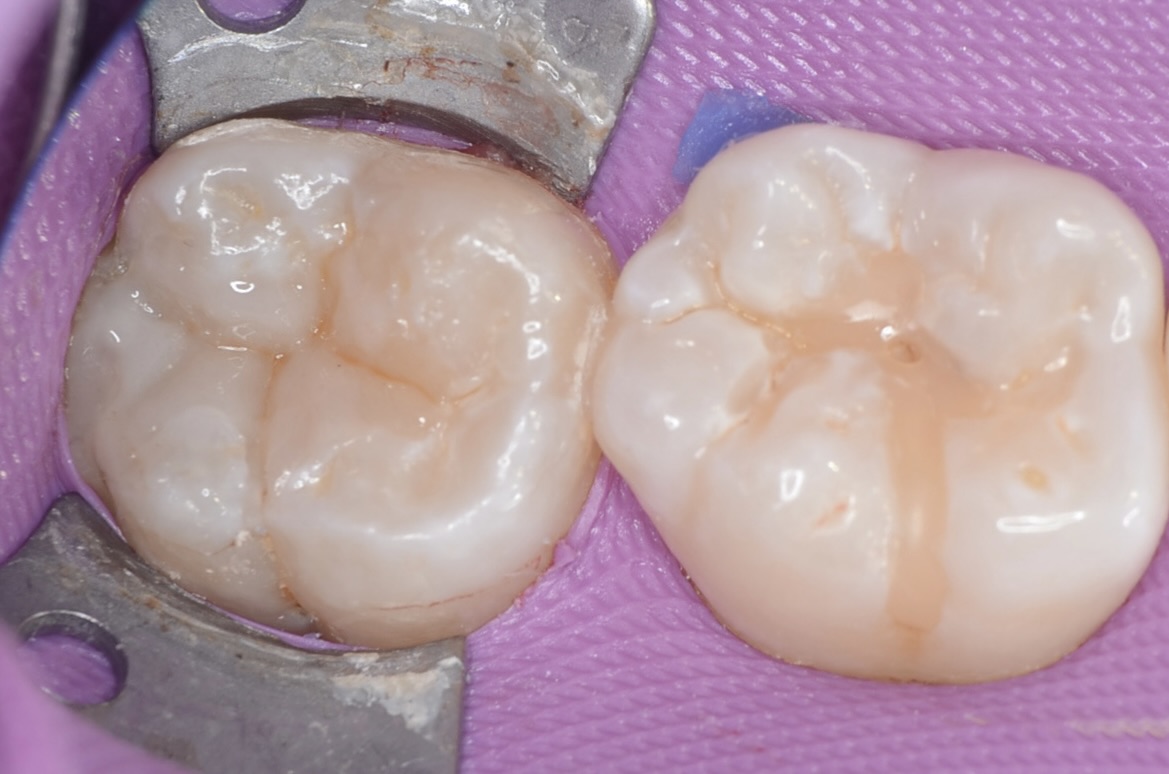

After

ダイレクトボンディング

天然歯の自然な形態を模倣してレジンを充填しました。 -

知覚過敏抑制材

虫歯は神経すれすれでしたが、露髄はしなかったので知覚過敏抑制材を象牙質にすり込みました。ハイドロキシアパタイトで象牙細管を封鎖することにより知覚過敏を抑制します。大きな虫歯の治療後は違和感が出やすいので予防的にこの様な処置もしています。 -

研磨後

研磨をしっかり丁寧にすることで、レジンと歯質の段差を修正し、虫歯になりにくくします。